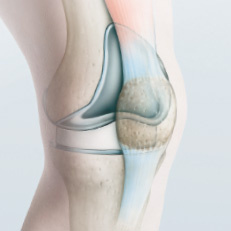

kniegelenkprothese_schnittblock

Abb. 1

Exakte und optimale Schnittführung dank ­patientenspezifischem Schnittblock

Die jüngste Entwicklung lehnt sich an die Zahnimplantat-Technik an. Ungefähr fünf Wochen vor dem Eingriff werden Gelenkachsen und Gelenkstellungen des Patienten mit einem Computertomogramm ausgemessen. Basierend auf diesen Daten konstruiert der Ingenieur des ­Knieprothesenherstellers am Computer ein virtuelles 3D-­Modell des Kniegelenks. An diesem interaktiven Modell bestimmt der Chirurg im Dialog mit dem Ingenieur die für den Patienten am besten geeignete Prothese und deren optimale Positionierung. Dabei verbinden sich medizinische Kenntnisse und Erfahrung mit theoretischem Ingenieurwissen über Statik und Dynamik. Anschliessend ­werden im 3D-Druckverfahren ein Kniegelenkmodell des Patienten sowie individuelle Schnittblöcke angefertigt (Abb. 1–5).

Beim Eingriff bringt der Operateur die Schnittblöcke auf den entsprechenden Gelenkteilen an, wo sie der exakten Schnittführung dienen. Mit ihrer Hilfe wird die Oberfläche zugeschnitten, auf der die Prothese angebracht wird (Abb. 6–7). Der Chirurg kann so deutlich schneller und präziser arbeiten. Zudem fallen die für die Implantation nötigen Zugänge kleiner und gelenkschonender aus als bei älteren computerassistierten Operationstechniken. Für die Patienten bedeutet das weniger Schmerzen, weniger Blutverlust, eine grössere Beweglichkeit und einen kürzeren Spitalaufenthalt.